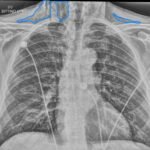

Subcutaneous emphysema (SE) is a rare but significant complication following dental procedures characterized by the presence of air in the subcutaneous tissue. This case report presents a 67-year-old male who developed right-sided facial swelling after tooth extraction, a procedure executed with high-power dental tools. Clinical findings included facial swelling and crepitus with no lip involvement, differentiating SE from an allergic reaction and hematoma. Diagnostic imaging through computed tomography (CT) and chest X-ray confirmed SE, showing diffuse subcutaneous air in facial and neck soft tissues. Initial management in the emergency department (ED) involved administration of antihistamines, corticosteroids, antibiotics, and otolaryngology (ENT) consultation with close monitoring for airway compromise. This case underscores the importance of including SE in differential diagnoses for post-dental procedure swelling, the effectiveness of CT imaging in SE identification, and the importance of early detection and treatment to prevent severe complications like respiratory and cardiac issues.